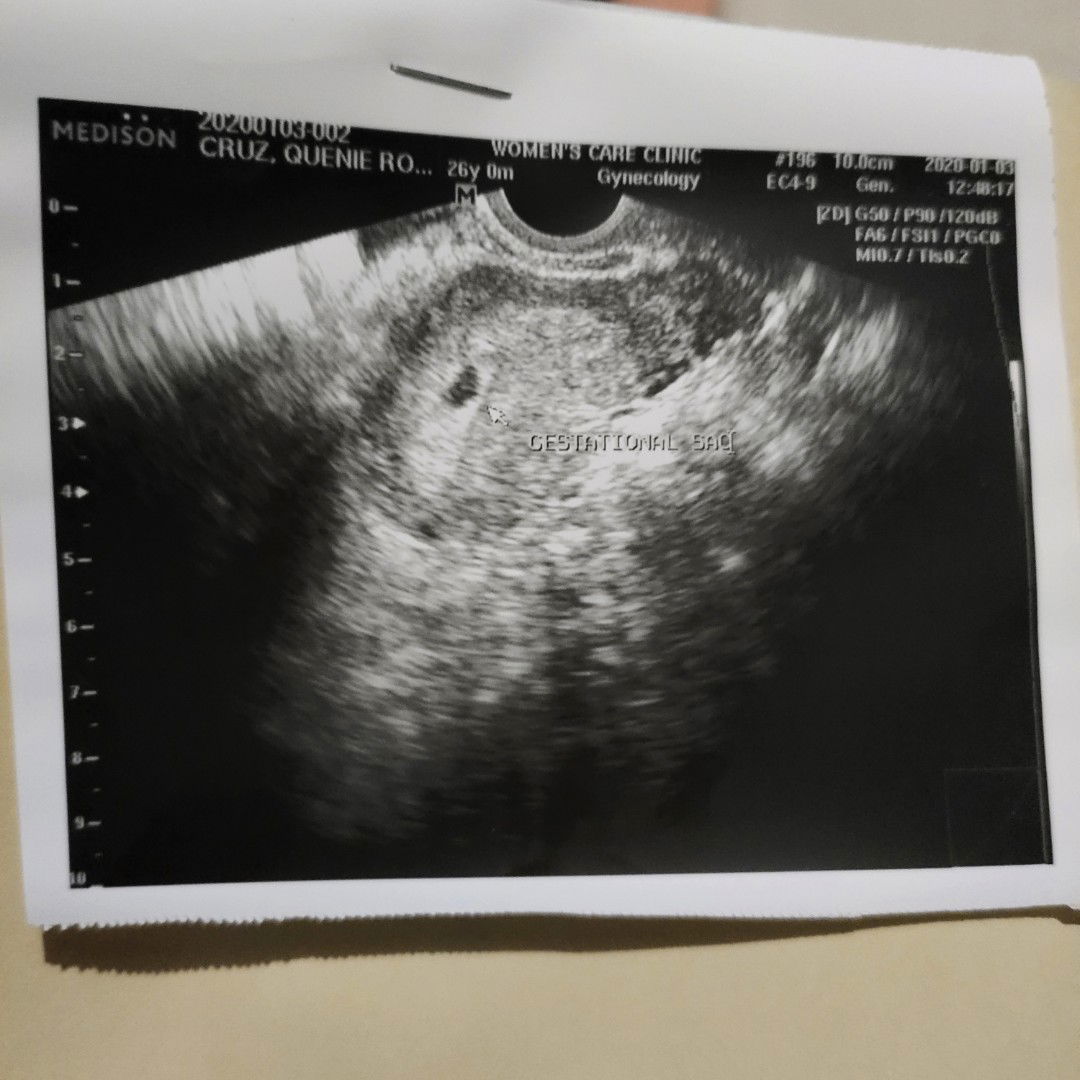

1st Baby

last menstruation ko po is nov. 16, 2019, then december 31 nung nalaman ko po na buntis ako at january 3 po yan po first check up ko yan po ung pic. then january 23, ng spotting po ako then chineck po ng ob ko ung baby ko kapag binased nya po sa last menstruation ko po dapat halos mg 2 months n po,ang sabi nya po may bahay bata na pero ung embryo ay hindi pa po nagdedevelop, normal lang po ba ung sitwasyon ko po?thank you po sa sagot

Answered 6y ago by Thrystyn Escano

Masyado pa siguro maaga yung unang TVS nyo. Try nyo po ulit habang wala pa sa 2nd trimester